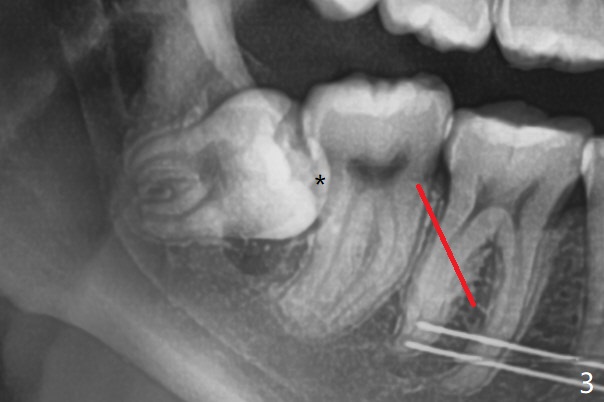

18岁女要求上大学前拔除智齿(图二),十三岁上四已经为了矫正而拔除(图一),所以现在只需要拔除下八,后者接近水平阻生,冠部可能位于下七远中颊侧(图三,四 *),所以附加切口应在七近中(红线)。智齿拔除后根部有两个牙槽窝(图五,六 *)。在右侧,塞入两个胶原塞(图七:1,2,collagen plug),其中一个末端剪开塞入根部牙槽窝。而左侧,使用一个胶原塞,但事先剪成两半(图八:1,3),第一部分也剪成燕尾,插入根部牙槽窝(1),然后在七远中放置骨水泥(1 cc Bond Apatite,2 红色),在后者上面放入胶原塞另外一半(3)。最后两侧都使用4-0 PGA 缝线。

使用胶原塞目的是预防干槽症,以前病例显示它促进骨化中心形成。骨水泥是一种医用性石膏(Biphasic Calcium Sulphate 硫酸钙 ),容易被身体吸收,3个月转换成自体骨。她哥哥(19岁)病例显示骨水泥与Osteogen Plug同样五个月会形成骨质。以后年轻人(25岁以下)智齿拔除不必植骨或者放置骨水泥。左下,右下智齿的确位于第二磨牙颊侧,事先附加切口近中,缝合后伤口不易裂开,骨粉丢失。拔除后即刻拍摄根尖片(图九,十),目的建立原有解剖,与愈合后比较,意外发现断裂牙片(F),后来取出。